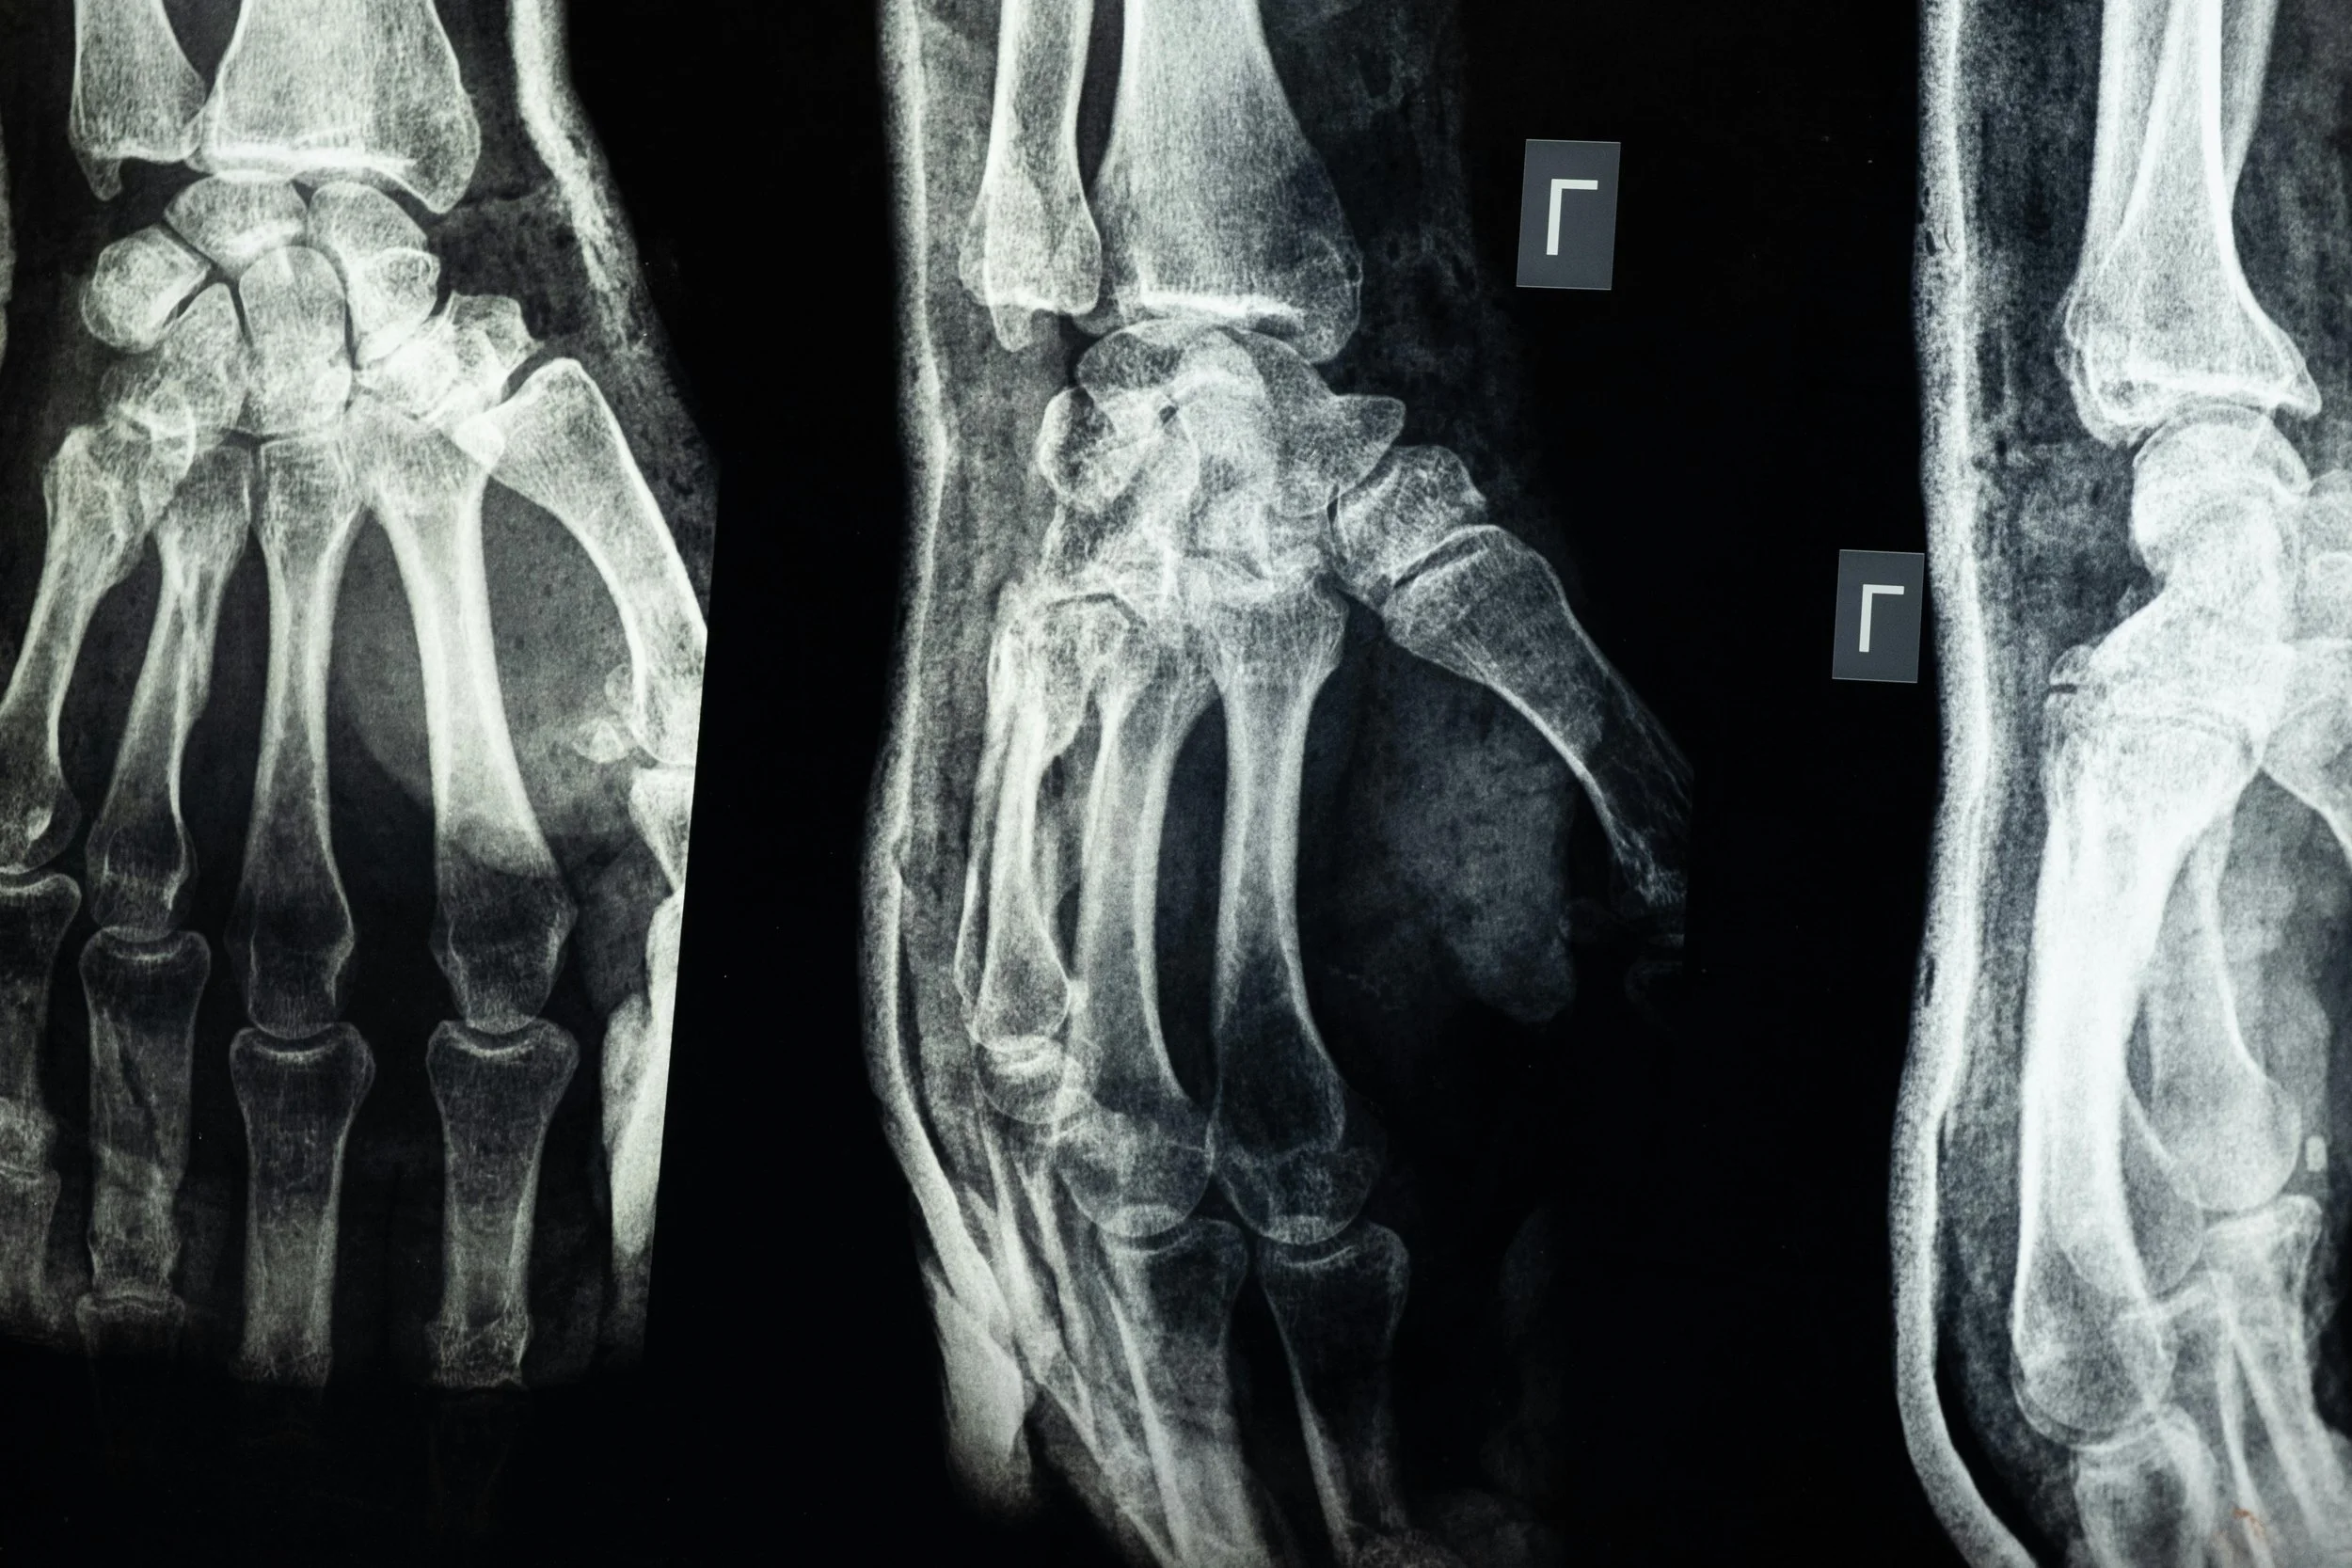

A recent case study in Northumbria, on GP x-ray referrals found that the average age of a patient being referred to the hospital by the GP for an x-ray was 82 years old. For most 82-year-olds, getting to the hospital is not a simple task, many do not drive at this age and would rely on public transport, a patient services ambulance or friends and family. When in hospital an 82-year-old is at an increased risk of getting a hospital acquired infection, add to this if a family member or friend has taken them to the hospital, this person will likely be sat in the waiting room with them, who is also at a risk of gaining a hospital acquired infection or possibly be the source of passing on an infection to others in the hospital. It is for this reason that the NHS is currently trying to find ways to prevent people from attending the hospital apart from those with the most urgent need to do so.

This is where RADray can help. By providing x-ray imaging in a location that is close to the patient’s home and in cases where travel is not an option for the patient, these services can even be provided in the comfort of the patient’s own home. With our online booking services, once a patient has been given a referral for an x-ray, they are able to book an appointment at a location that is convenient for them at a time to suit them and for patients that do not wish to use online features, there is the option to call RADray to make the same appointment. GP surgeries are far more common than hospitals and are generally in close proximity to the patient’s house, making travel easier for the patient. By giving patients appointment slots, we are able to reduce the length of time the patient has to wait for their procedure; we also have the ability to provide ad hoc appointments. Should a patient be seen by the GP and RADray are in the surgery or a surgery nearby, the GP would be able to refer the patient for a same day x-ray, saving the patient time and enabling them to start treatment sooner.

The staff at RADray have all been “Red Dot” trained, allowing them to give the referring clinician an instant prognosis, allowing them to start treatment earlier and enable to the patient to recover quicker. With our contract for reporting, we are able to guarantee that all x-rays have a full and final diagnosis available for the referring doctor within 48 hours of the patient attending their appointment.

Through several freedom of information requests, 13 NHS Trusts were contacted in the North-West, covering a total of 36 hospitals. For the year 2022, these hospitals caried out a total of 1,024,242 GP x-rays, that could be carried out by RADray. Of this number only 152801 results were made available to the GP in under 48 hours, equating to just under 15% of patients x-rayed. RADray has the capacity to x-ray and report all of the patients seen by the company within 48 hours of the patient attending their appointment. With any illness, the quicker treatment can be started, the better the outcome is for the patient, the patient returns to health quicker and the patient has a better experience of the healthcare system.